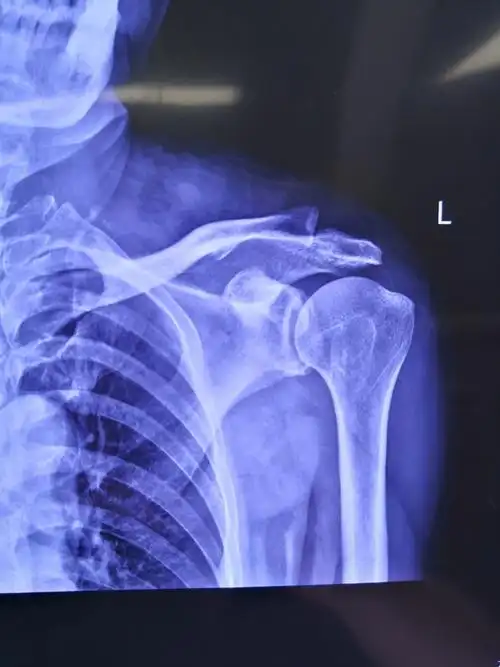

肱骨骨折x线照片.

关节活动受限,疼痛.诊断:肩袖损伤,腋神经损伤 病案号:1907